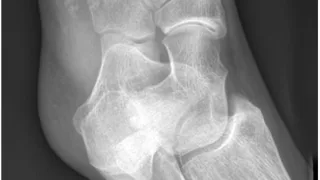

午前の病院での仕事今朝は, 曇.雲が厚く, 部屋の中が薄暗かったので, 電灯を点けました.雨の予報ですが, 午後には上がるとのこと.8時前に病棟に上がって, 8時から朝の病棟回診.昨日, 足関節部の神経鞘腫を摘出した患者さんは, つま先を曲...